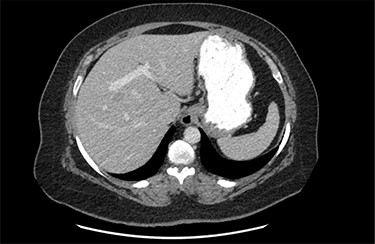

On assessment, the patient denied any symptoms related to her neuroendocrine tumor, including flushing, increased sweating, increased heart rate, wheezing, shortness of breath, diarrhea, weight loss or appetite changes. The only significant family history was a paternal and maternal grandfather with colon cancer. Imaging results were significant for computed tomography (CT) of chest demonstrating very small, but multiple, pulmonary nodules. A CT abdomen and pelvis demonstrated the known neuroendocrine tumor near the ileocecal valve (Fig. 1) as well as two poorly visualized liver lesions (Figs 2–4). The magnetic resonance imaging (MRI) demonstrated two separate one-centimeter lesions in segment 5 and 7 of the liver (Figs 5 and 6). The portal vein lacked normal left and right bifurcation; there was a circumferential right portal vein, which coursed anteriorly and superiorly and ultimately to the left lobe of the liver.

MRI image again demonstrating segment 5 metastatic lesion in close proximity to portal vein.